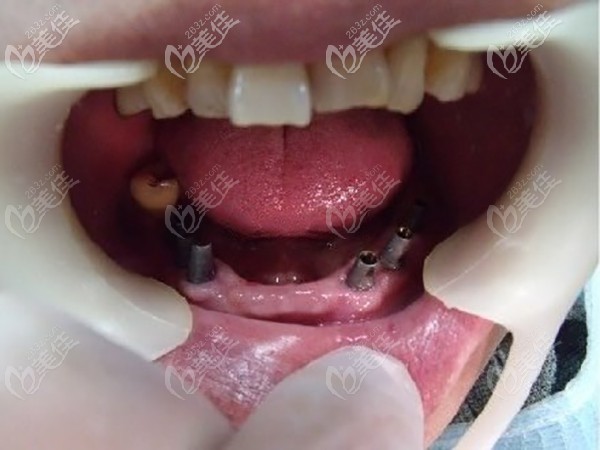

術后照片:

種植體:德國icx ALL-ON-6種植修復。

在麻藥的作用下,很快就種好牙齒,醫(yī)生說術后根據個人體質不同,有的人沒感覺,有的人只會有輕微腫脹不適,不會有很大的疼痛,老人說他自己沒啥感覺。

老人戴完牙冠后,自己還是比較滿意的,昆明柏德口腔種植牙價格在當地收費還是比較合理的,重要的是老人能有一口吃啥都香的牙齒,兒子沒有花多少錢就體現(xiàn)了孝心,還有比這更好地事情么?